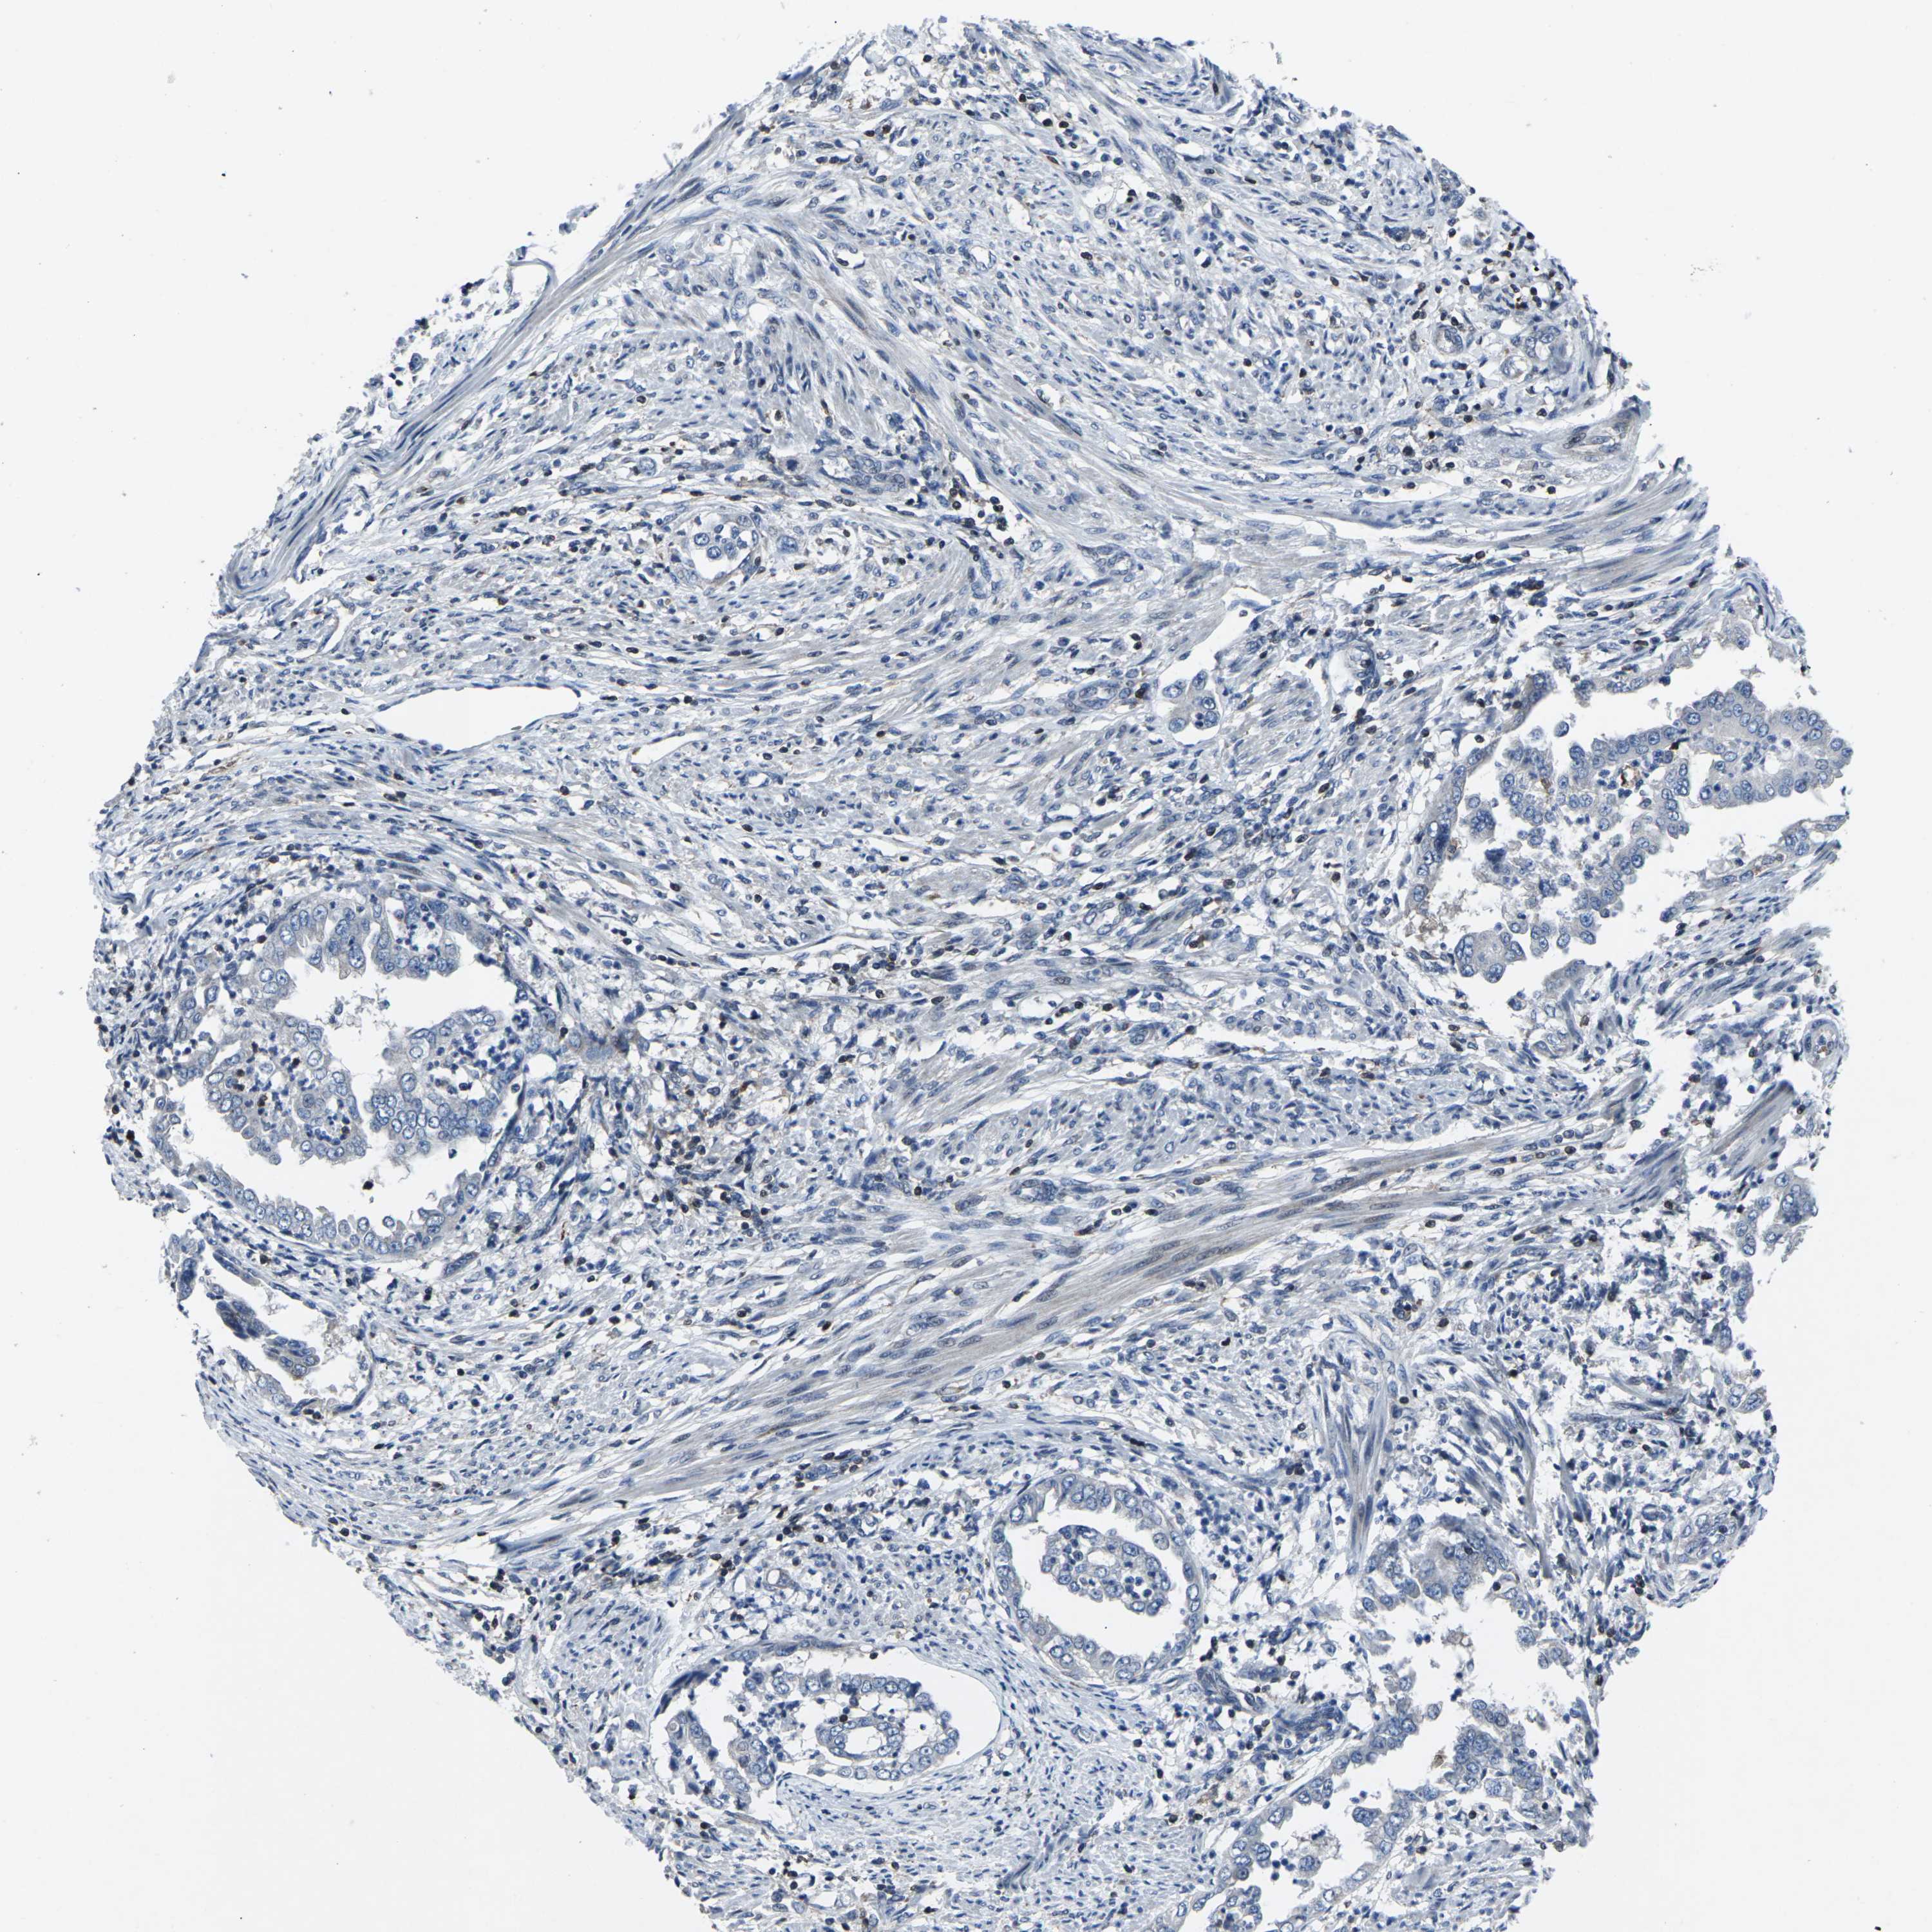

ENDOMETRIAL CANCER - Protein expressioni

A mouse-over function shows sample information and annotation data. Click on an image to view it in a full screen mode. Samples can be filtered based on level of antibody staining by selecting one or several of the following categories: high, medium, low and not detected. The assay and annotation is described here.

Note that samples used for immunohistochemistry by the Human Protein Atlas do not correspond to samples in the TCGA dataset.

Antibody stainingi

Antibody staining in the annotated cell types in the current human tissue is reported as not detected, low, medium, or high, based on conventional immunohistochemistry profiling in selected tissues. This score is based on the combination of the staining intensity and fraction of stained cells.

Each image is clickable and will lead to virtual microscopy that enables deeper exploration of all samples and also displays staining intensity scores, fraction scores and subcellular localization as well as patient and tissue information for each sample.

Antibody HPA001860

Antibody CAB013108

Staining

High

Medium

Low

Not detected

Intensity

Strong

Moderate

Weak

Negative

Quantity

>75%

75%-25%

<25%

None

Location

Nuclear

Cytoplasmic/membranous

Cytoplasmic/membranous,nuclear